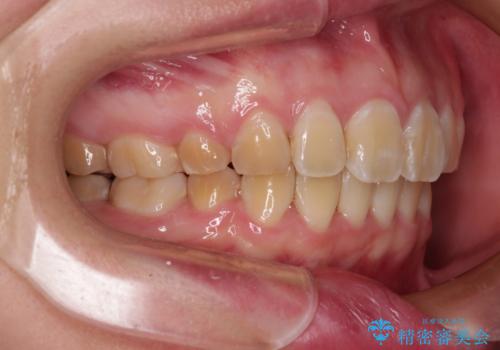

- 口元の閉じにくさと、前歯のでこぼこの歯並びを気にして来院された患者様です。

口元を積極的に引っ込めるために、上下左右の小臼歯計4本を抜歯することとしました。

4本の歯を抜歯したことで、飛び出していた口元が引っ込み、横顔が大きく改善されました。